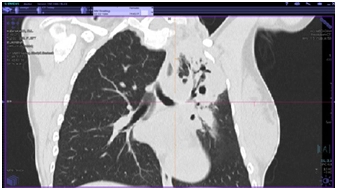

КТ органов грудной клетки (от 17.08.2017 г.)

Заключение: массивные инфильтративные изменения в верхней доле левого легкого полностью неясного генеза, возможно имеет место как воспалительный специфический характер поражения с распадом, так и осложнение пневмонии с формированием абсцесса, злокачественный процесс с распадом мало вероятен.